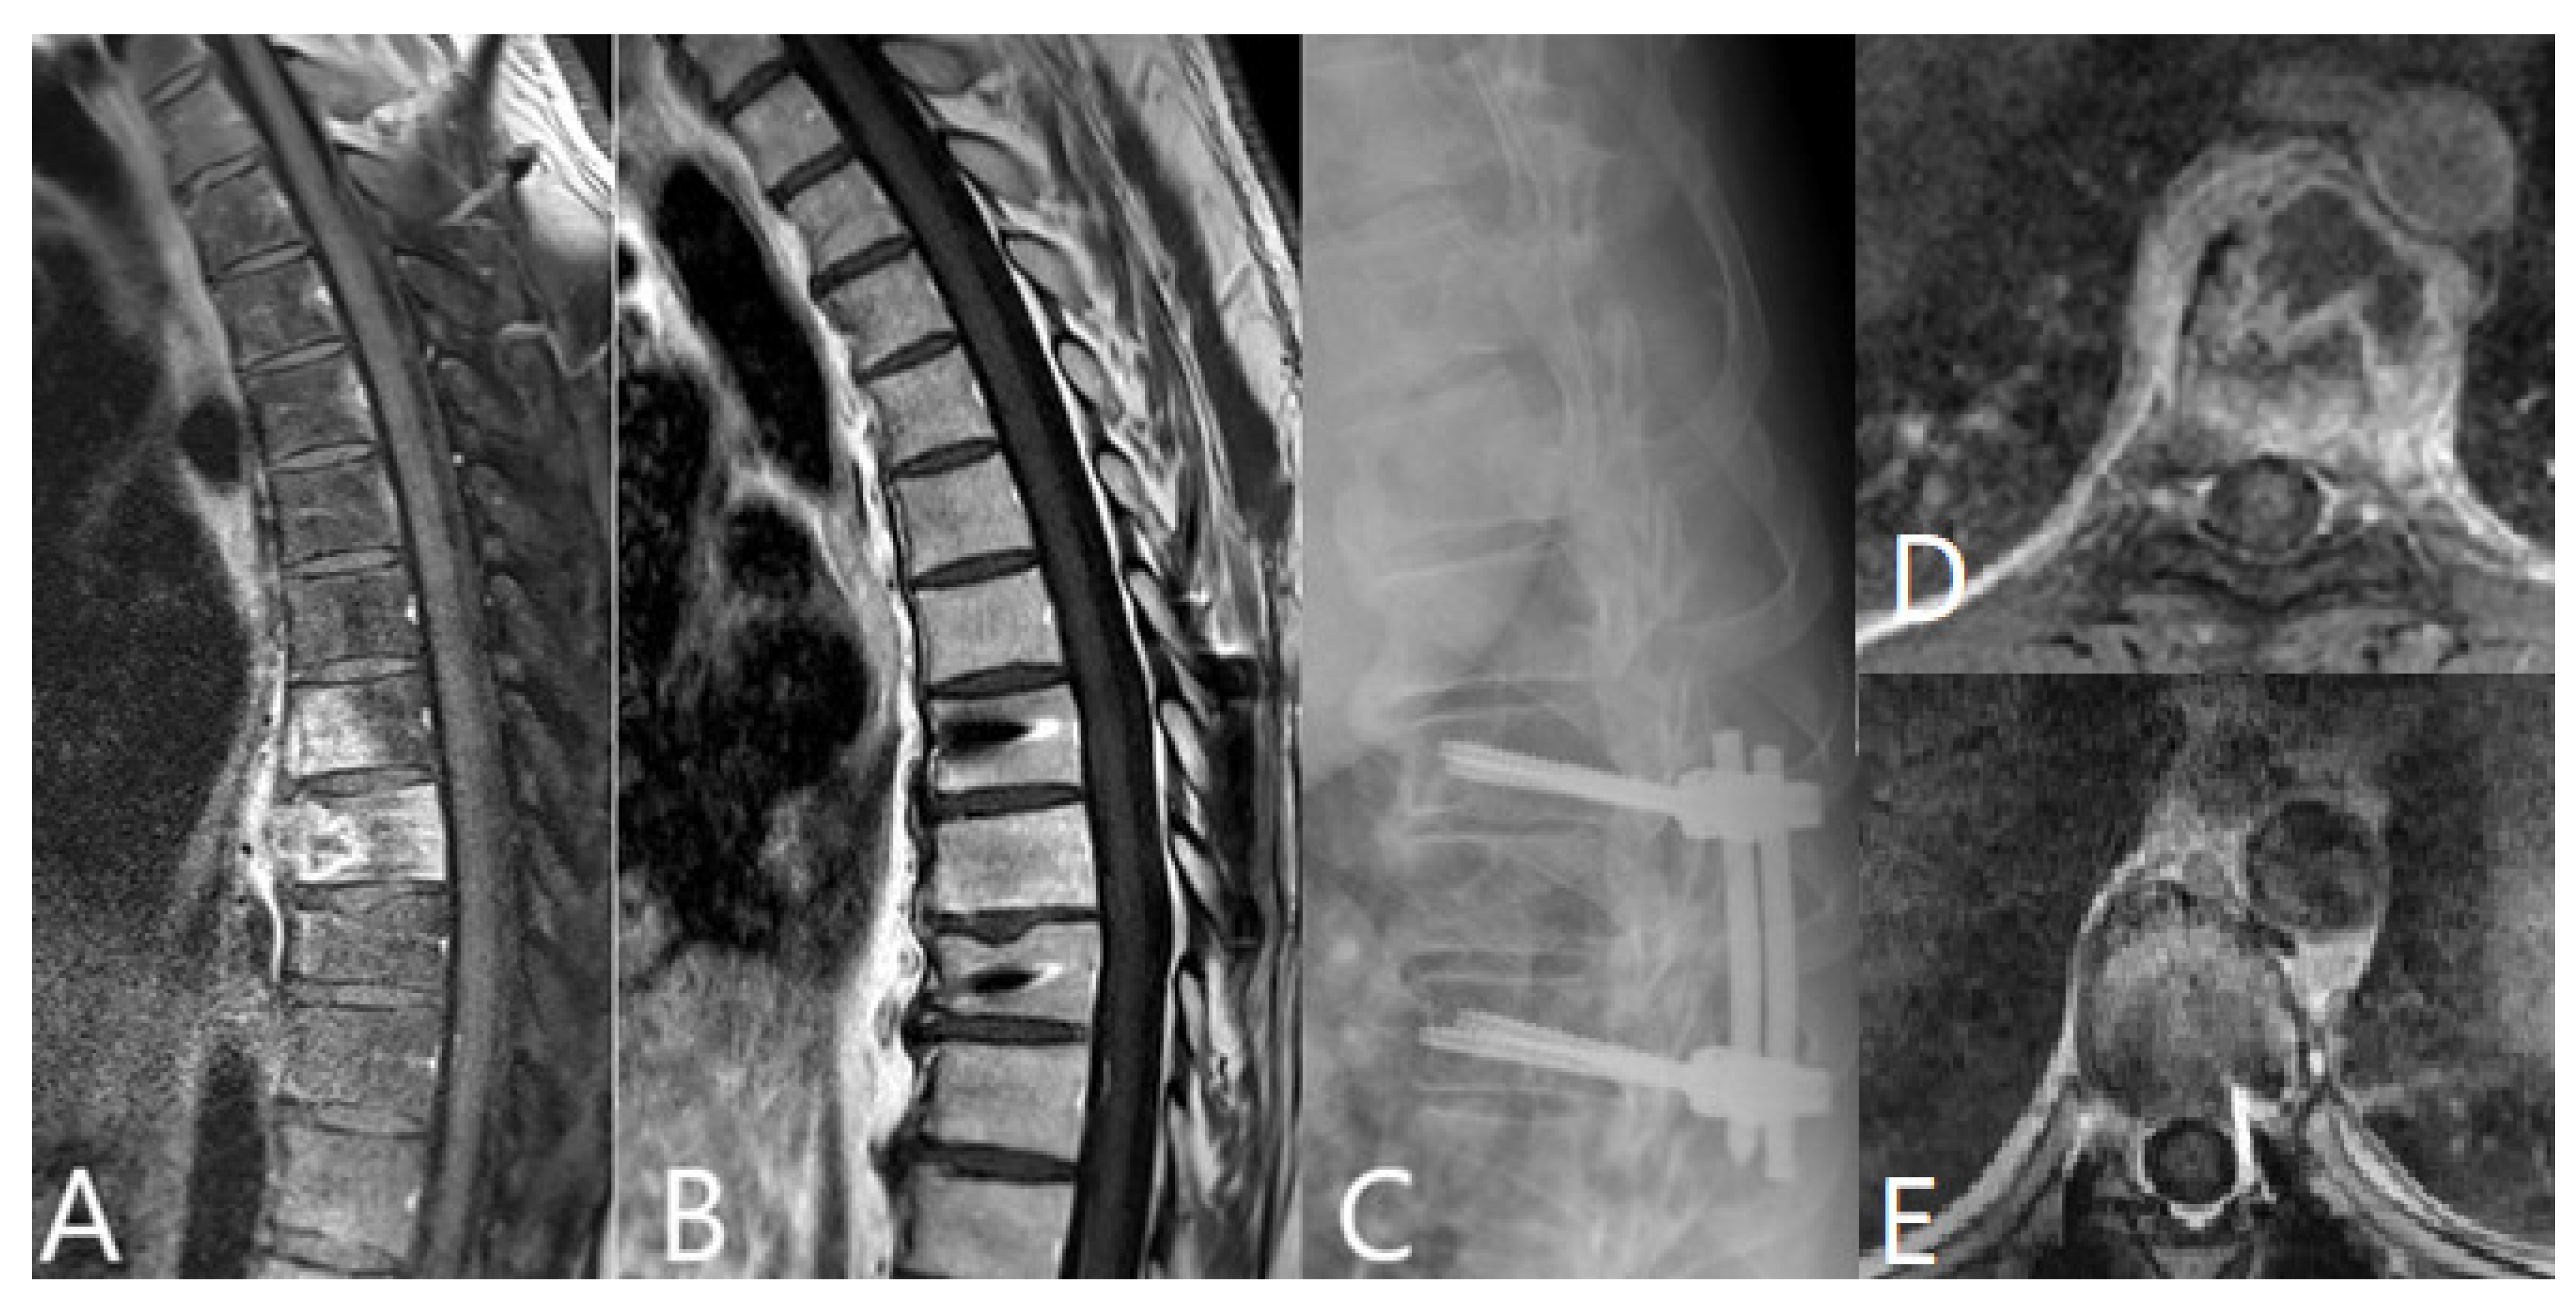

| Thoracic and lumbar spine | |

| Decompression and empyema evacuation without stabilization | 54 |

| Dorsal stabilization | 138 |

| Without cage | 36 |

| With cage | 102 |

| TLIF (Transforaminal interbody fusion) PEEK Cage | 45 |

| TLIF Titan Cage | 35 |

| XLIF (Extreme lateral interbody fusion) PEEK Cage | 22 |